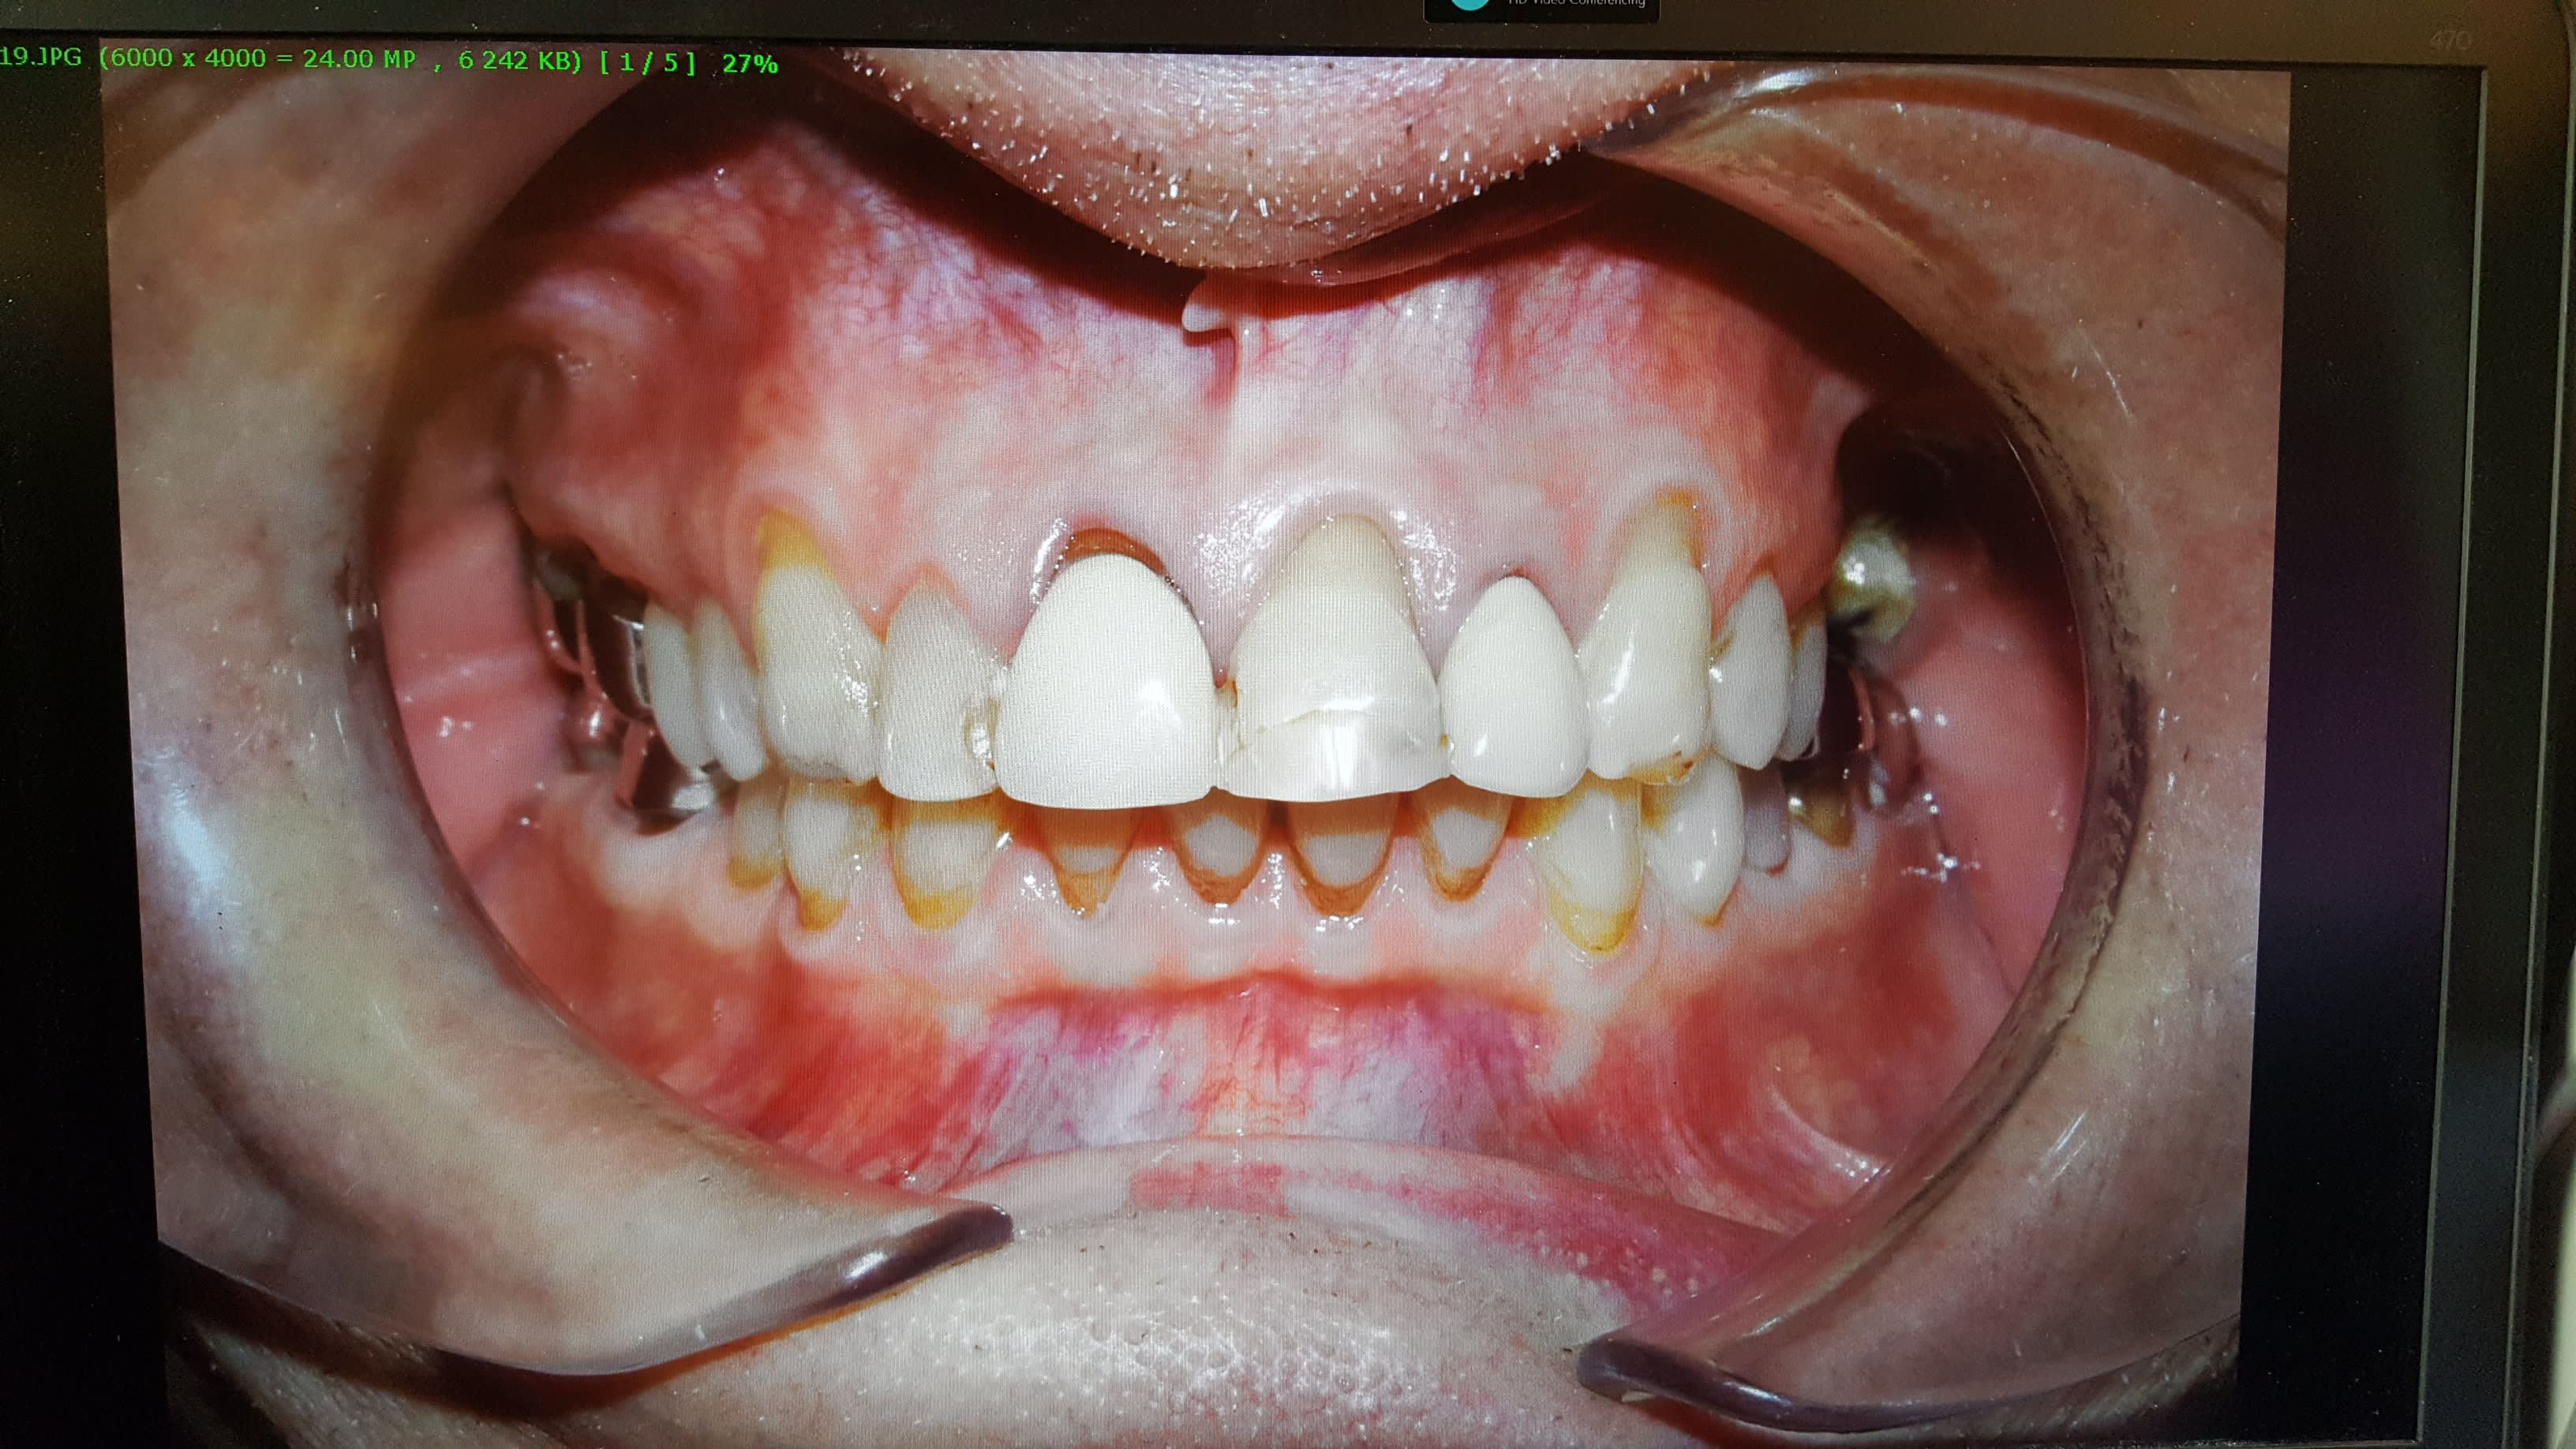

Pour ce qui est des joues : j ai 4 ou 5 types d écarteur différents. Il faut trouver celui bien adapté au patients (En particulier pour l ortho ou la taille des bouches varie tout le temps).

Pour un adulte en omni : pour les secteur latéraux soit les miroir pour des supers photos mais les patients n aiment pas bcp, Soit des ecateurs assez echancrés.